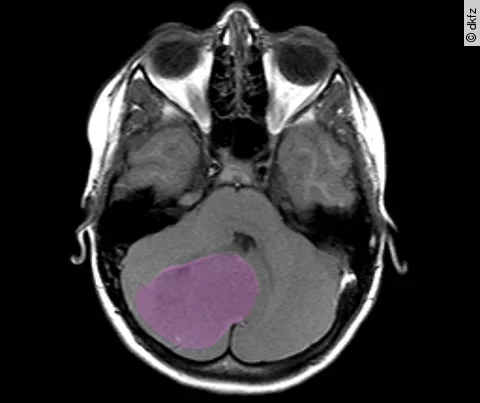

Überraschende genetische Vielfalt bei kindlichen Hirntumoren

18.08.17

| News

| Panorama